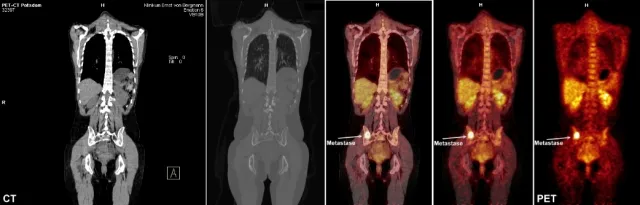

Die fortschrittliche GE VUE Point HD iterative 3D-Rekonstruktion verbessert die Auflösung bei exzellenter Bildqualität. Auch kleine Läsionen können so entdeckt und die quantitative Genauigkeit erhöht werden.